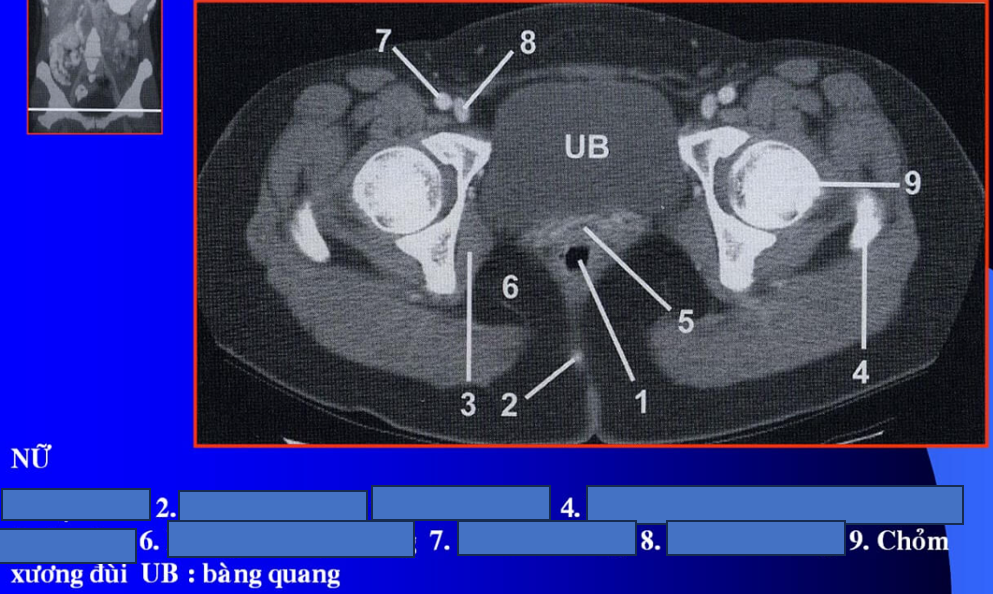

cq trong hình ?

cơ tl? cơ chậu?